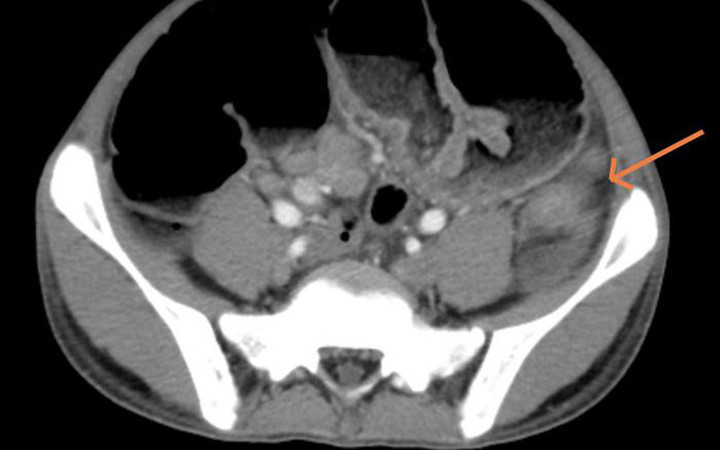

Hình ảnh cắt lớp vi tính ổ bụng của bệnh nhi.